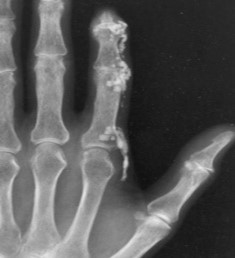

עם התקדמות Scleroderma יכול להופיע קיבעון של המפרקים (קונטרקטורות, Contractures), שינוי בצורת האצבעות (Sclerodactyly) ונסיגה של קצות האצבעות (Acro-osteolysis) והופעת Calcinosis בעור ורקמות רכות האופייניים לשתי הצורות של Scleroderma, מוגבלת ונרחבת. הבדלים במהלך קליני של מחלה "צעירה" (עד 5–7 שנות מחלה) ומחלה "מאוחרת" בולטים בעיקר ב-Scleroderma נרחבת (DcSSc); הבדלים אלו פחות בולטים במחלה מסוג Scleroderma מוגבלת (LcSSc).

ביופסיית עור בשלבים המוקדמים של Scleroderma מדגימה הסננה של העור והרקמות התת-עוריות על ידי תאי דלקת ושקיעה של סיבי Collagen סביבם. עם השנים עיבוי העור נסוג במידה מסוימת, אך מותיר עור צלקתי, עם שינויים בצבע באזורים הנגועים. השינויים באצבעות (Sclerodactyly) אינם הפיכים; עיוותים של אצבעות וקיבעון (קונטרקטורות) במפרקים גורמים להפרעה בתפקוד הידיים ולהגבלה בטווח התנועה במפרקים.

כיבים בעור מופיעים במחצית מחולי ה-Scleroderma. מיקומם בדרך כלל בקצות האצבעות אך הם עשויים להופיע גם במקומות בהם העור מתוח: מעל מפרקי כפות הידיים או מעל המרפקים. הופעת פצעים בבהונות הרגליים יחסית נדירה. שליש מהחולים סובלים מכיבים חוזרים בעלי אופי עקשני עם נמק ונטייה לזיהום ברקמות. לאחר ריפוי הכיבים, נותרת בקצות האצבעות צלקת עגולה וקעורה, הנקראת Pitting Scar.